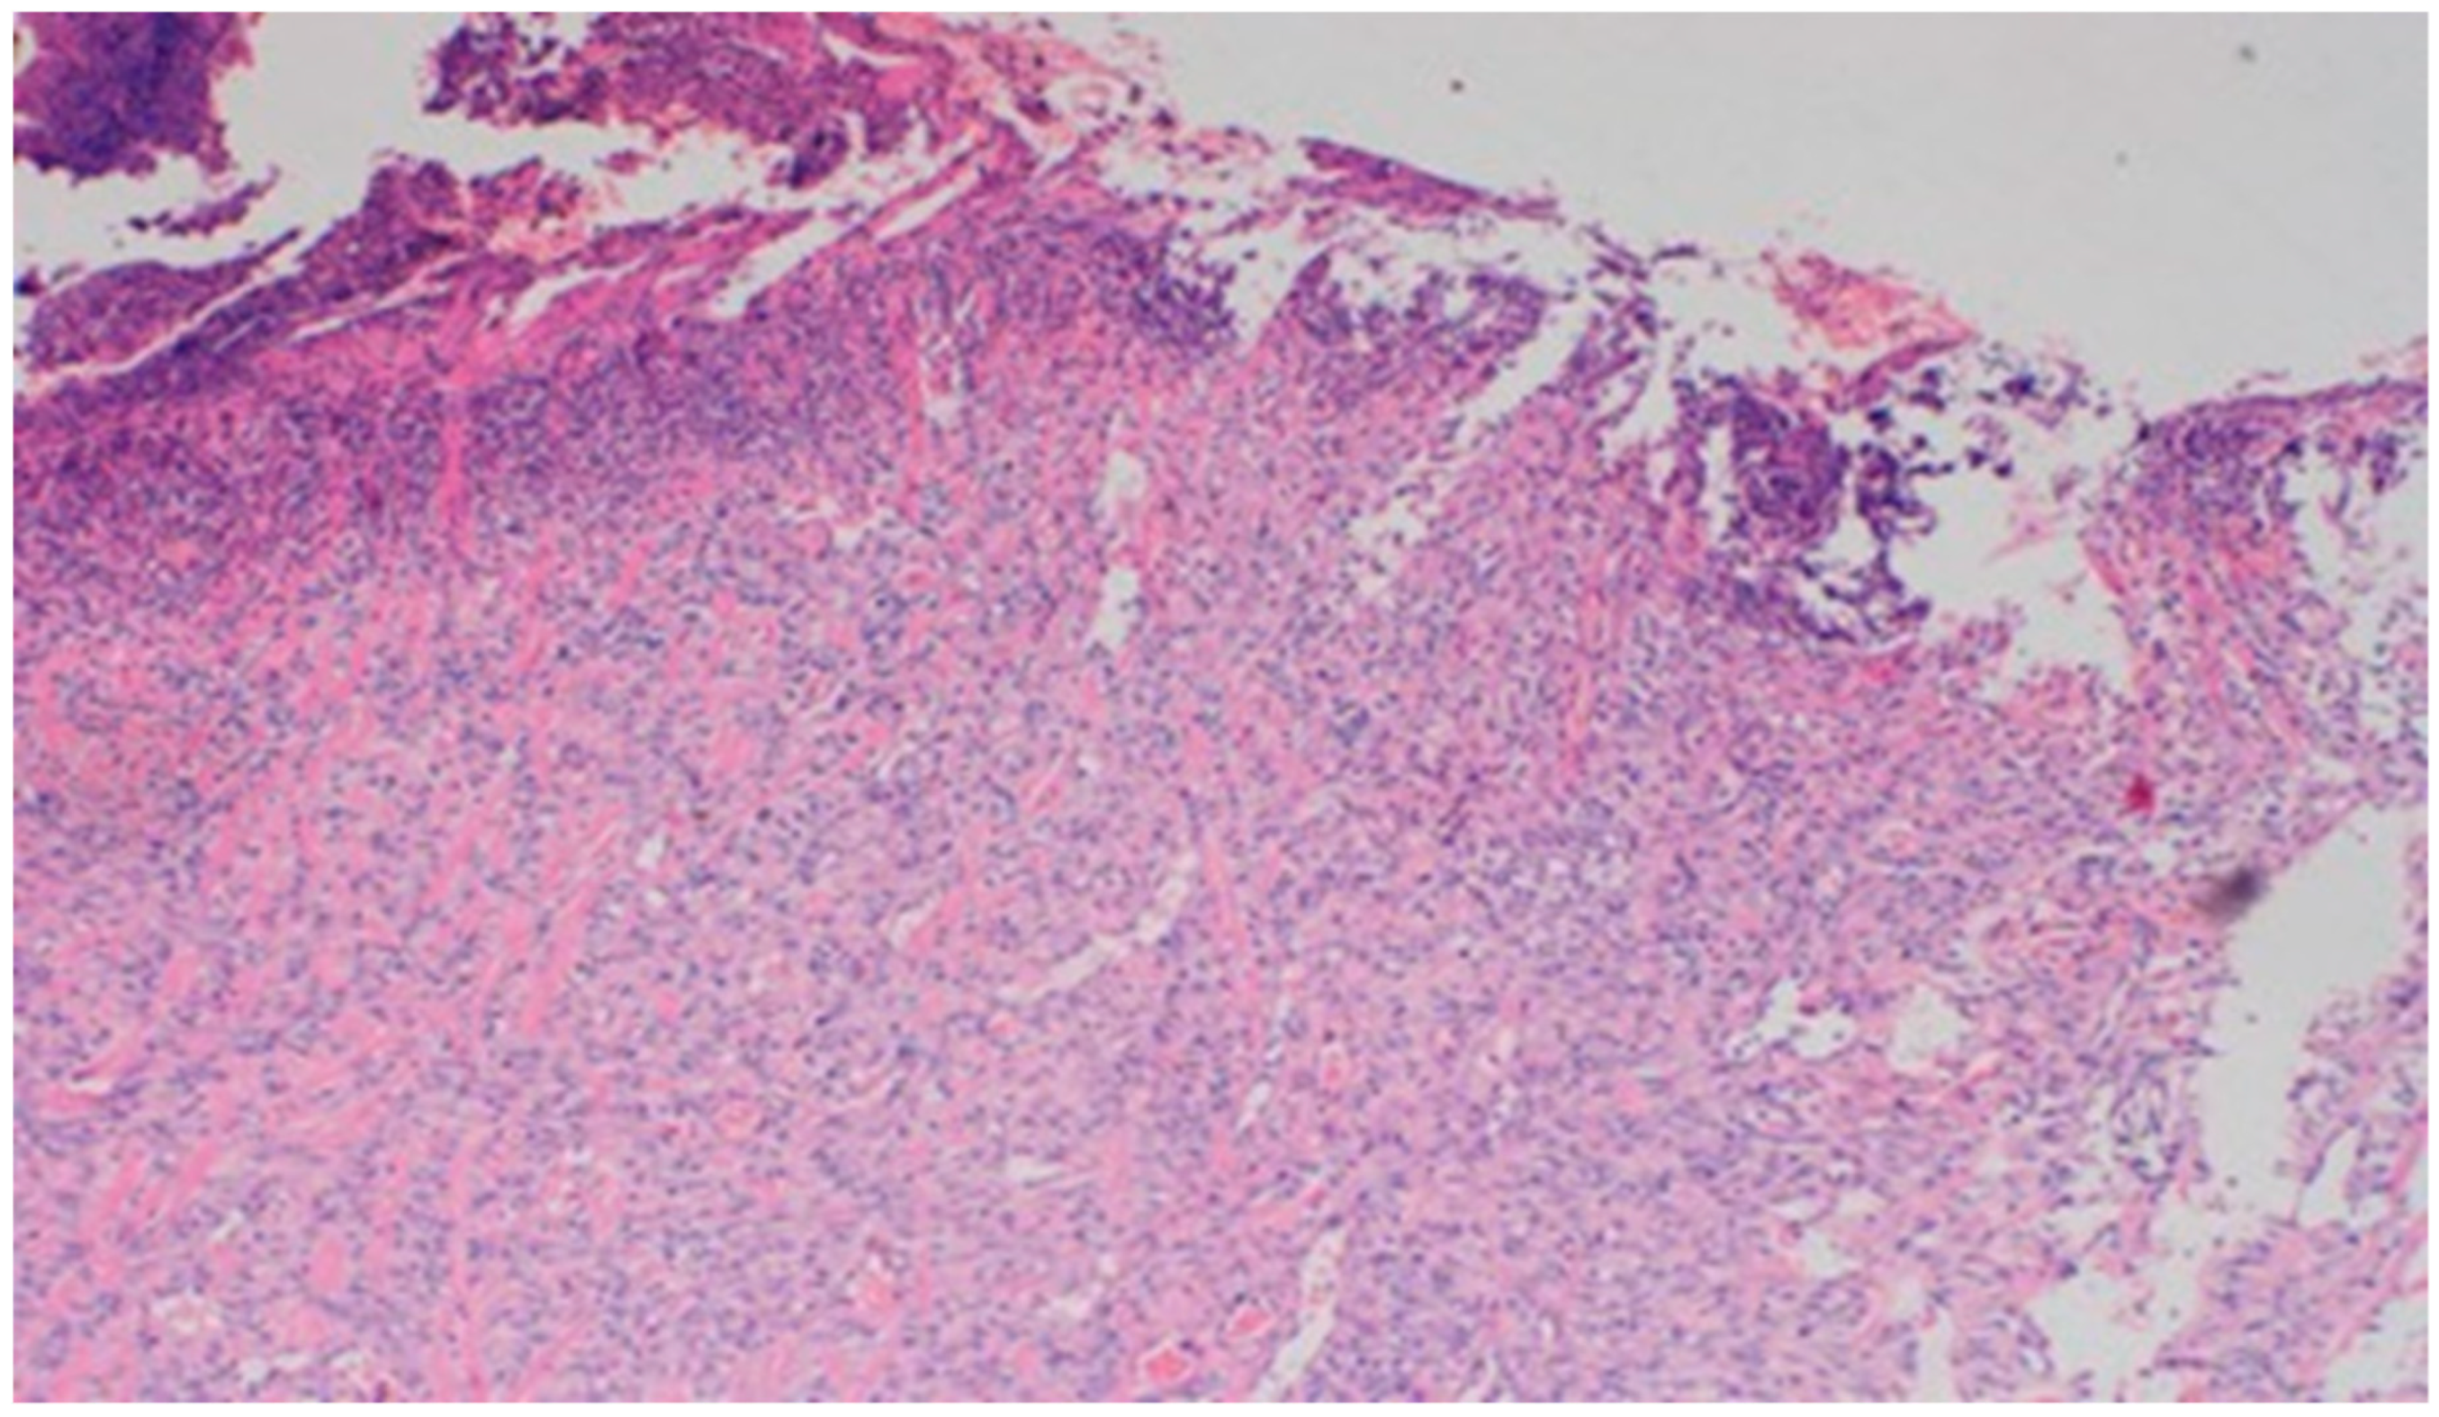

On day 15, the wound samples examined differed significantly, depending on the therapeutic agent used. The wound treated with the 1% propolis ointment was characterized by a consistently slight epidermization and moderate neovascularization, as was on day 10; however, the wound showed no foci of superficial necrosis. Additionally, the type of inflammatory infiltration changed into a lymphocytic-granulocytic one. The wound in the experimental group D2, treated with the 1% nanosilver ointment, and the wound in control group K, treated with sulfathiazole, continuously showed the progression of inflammation, from moderate to severe. On day 15, the wounds from the experimental group D2 and control group K were covered with large superficial necrosis.

The wound treated with the 1% nanosilver ointment showed high neovascularization, with no epidermization at the same time. The wound from group D3, treated with a mixture of 1% propolis and 1% nanosilver, showed a constant moderate inflammatory infiltration, however, with a change of type on day 15 to lymphocytic-granulocytic. Additionally, on day 15, the wound in the D3 experimental group was covered with a slight superficial necrosis with moderate neovascularization. The wound showed no signs of epidermization. The histopathological findings from day 15 are presented in Table 10 and Figure 18 and Figure 19.

Figure 19. Superficial necrosis. Major neovascularization (40×, H-E) in the wound treated with the 1% nanosilver ointment on day 15.